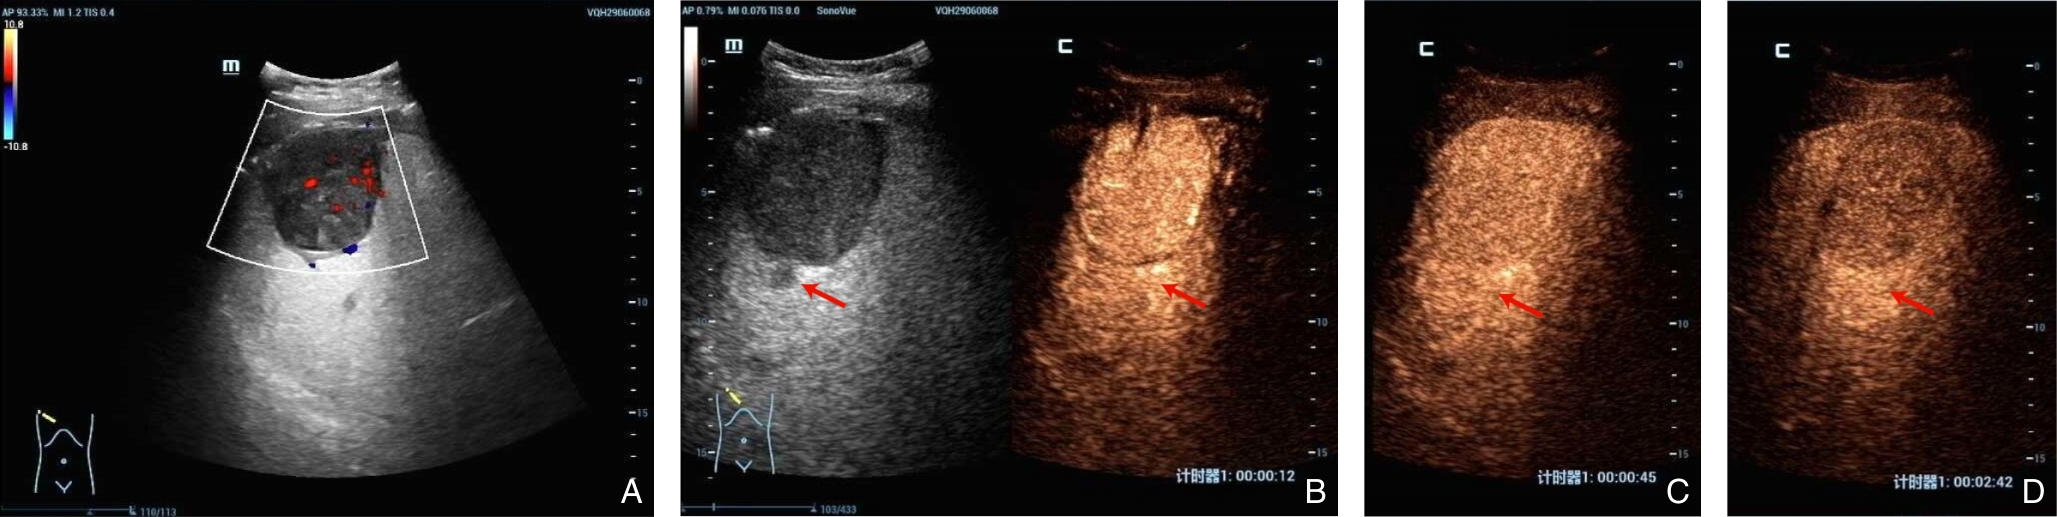

Background and Aims Hepatocellular carcinoma (HCC) presenting initially with bone metastasis is uncommon, and metastasis to the appendicular skeleton is particularly rare. These cases often lack typical liver disease history, elevated alpha-fetoprotein (AFP), or characteristic imaging findings, leading to frequent misdiagnosis or delayed diagnosis. This study reports a rare case of occult HCC presenting with humeral metastasis and reviews the literature to improve clinical recognition and management.Methods The clinical data of a 42-year-old male patient presenting with humeral metastasis as the initial manifestation admitted in August 2025 were retrospectively analyzed, including laboratory tests, multimodal imaging findings, histopathological and immunohistochemical results, treatment, and follow-up outcomes. Relevant literature was also reviewed.Results The patient presented with left shoulder pain. Imaging revealed osteolytic destruction of the left humerus. PET/CT incidentally detected multiple hepatic lesions without significant FDG uptake. Contrast-enhanced ultrasound demonstrated atypical enhancement patterns, initially suggesting a perivascular epithelioid cell tumor. Histopathological and immunohistochemical examination of biopsy specimens from both the humeral and hepatic lesions confirmed moderately differentiated hepatocellular carcinoma with humeral metastasis (CNLC stage IIIb). The patient received systemic therapy with sintilimab plus bevacizumab, followed by transcatheter arterial chemoembolization. After 6 months of follow-up, the intrahepatic lesions had decreased in size, the bone metastasis remained stable, and pain symptoms were significantly relieved.Conclusion HCC presenting with humeral metastasis as the initial manifestation is extremely rare and may lack typical imaging and serological features. Clinicians should consider HCC in patients with unexplained bone metastasis even in the absence of liver disease history or elevated AFP. Multimodal imaging and pathological biopsy are essential for accurate diagnosis and appropriate management.